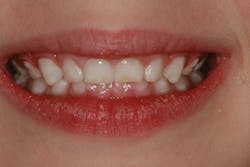

Even if a child does not have sleep apnea, sleep and breathing habits can have a profound impact on the growth and development of the face and airway. We know that the position and strength of the oral musculature can have dramatic effects on the growth and development of the arches and facial structure. When a person breathes through the mouth, the tongue cannot sit up on the roof of the mouth and expand the arches laterally and anteriorly. The results can be seen in the photo below of a 4-year-old patient who is a chronic mouth breather. The primary teeth should have spacing between them. In this case, the teeth have collapsed inward due to perioral muscle pressure and a lack of outward tongue pressure. The tongue is not exerting outward pressure because it is between the occlusal surfaces of the teeth to facilitate mouth breathing. Also note the dry, cracked lips and swollen gingival margins that result from mouth breathing.